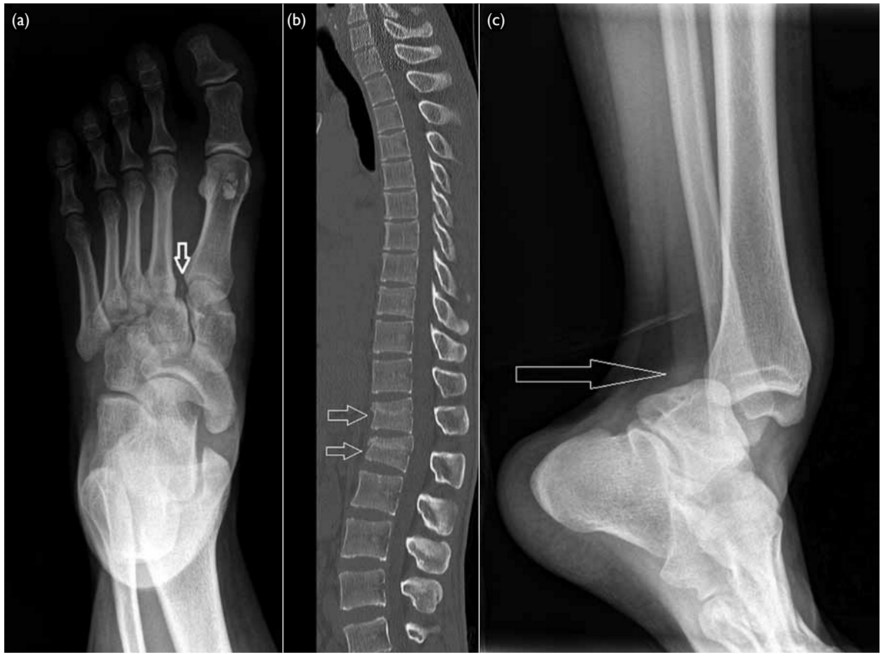

足首 脱臼 骨折

足関節脱臼骨折 足の外科虎の穴